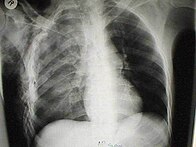

Les cas importants d'emphysème sous-cutané sont faciles à diagnostiquer en raison des signes caractéristiques de l'affection. Dans certains cas, les signes sont subtils, ce qui rend le diagnostic plus difficile. L'imagerie médicale est utilisée pour diagnostiquer la maladie ou confirmer un diagnostic établi à l'aide de signes cliniques. Sur une radiographie du thorax, l'emphysème sous-cutané peut être vu comme des stries radiotransparentes dans le modèle attendu du groupe de muscles principaux du pectoral. L'air présent dans les tissus sous-cutanés peut interférer avec la radiographie du thorax, ce qui peut masquer des affections graves comme le pneumothorax. Elle peut également réduire l'efficacité de l'échographie thoracique. D'autre part, comme l'emphysème sous-cutané peut être visible sur les radiographies du thorax avant un pneumothorax, sa présence peut être utilisée pour déduire celle de cette dernière lésion. L'emphysème sous-cutané peut également être observé sur les scanners, les poches d'air apparaissant comme des zones sombres. Le scanner est si sensible qu'il permet généralement de trouver l'endroit exact d'où l'air pénètre dans les tissus mous. En 1994, M. T. Macklin et C. C. Macklin ont publié d'autres aperçus sur la physiopathologie du syndrome de Macklin spontané survenant à la suite d'une grave crise d'asthme. La présence d'un emphysème sous-cutané chez une personne qui semble très malade et fébrile après une crise de vomissements suivie d'une douleur thoracique gauche est très évocatrice du diagnostic du syndrome de Boerhaave, qui est une urgence vitale causée par une rupture de l'œsophage distal. L'emphysème sous-cutané peut être une complication de l'insufflation de CO2 avec la chirurgie laparoscopique. Une augmentation soudaine du CO2 en fin de marée après la hausse initiale qui se produit avec l'insufflation (les 15-30 premières minutes) devrait faire suspecter un emphysème sous-cutané. Il est à noter que l'oxymétrie de pouls et la pression des voies aériennes ne varient pas dans l'emphysème sous-cutané, contrairement à l'intubation endobronchique, au capnothorax, au pneumothorax ou à l'embolie au CO2.